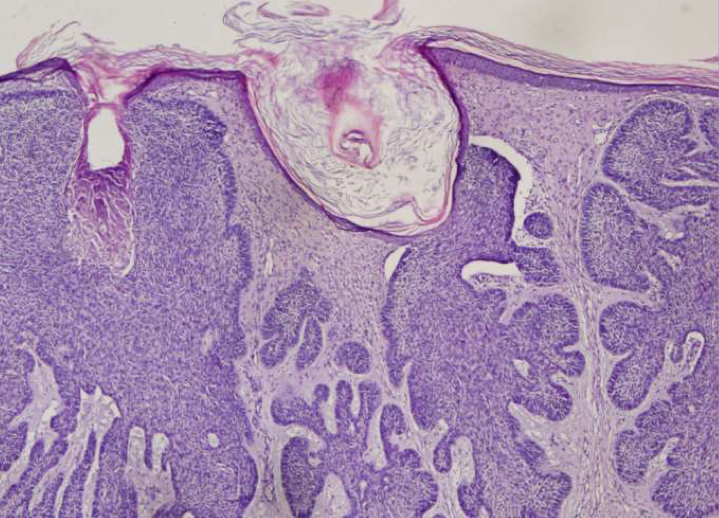

Pourquoi parle-t-on de carcinome basocellulaire ?

→ Parce que les cellules cancérisées sont les kératinocytes de la couche basale de l’épiderme.

De quoi sont constitués les bourgeons observés dans le carcinome basocellulaire ?

→ De cellules basales cancéreuses.

→ Elles sont confinées dans l’épiderme et ne dépassent pas la membrane basale.

Quelle est la caractéristique de la forme superficielle du carcinome basocellulaire ?

Que montre l’image où la tumeur envahit le derme ?

→ Une extension tumorale profonde dans le derme.

Quelle est la disposition histologique typique des cellules dans le carcinome basocellulaire ?

→ Une disposition en palissade : caractéristiques des carcinomes basocellulaires